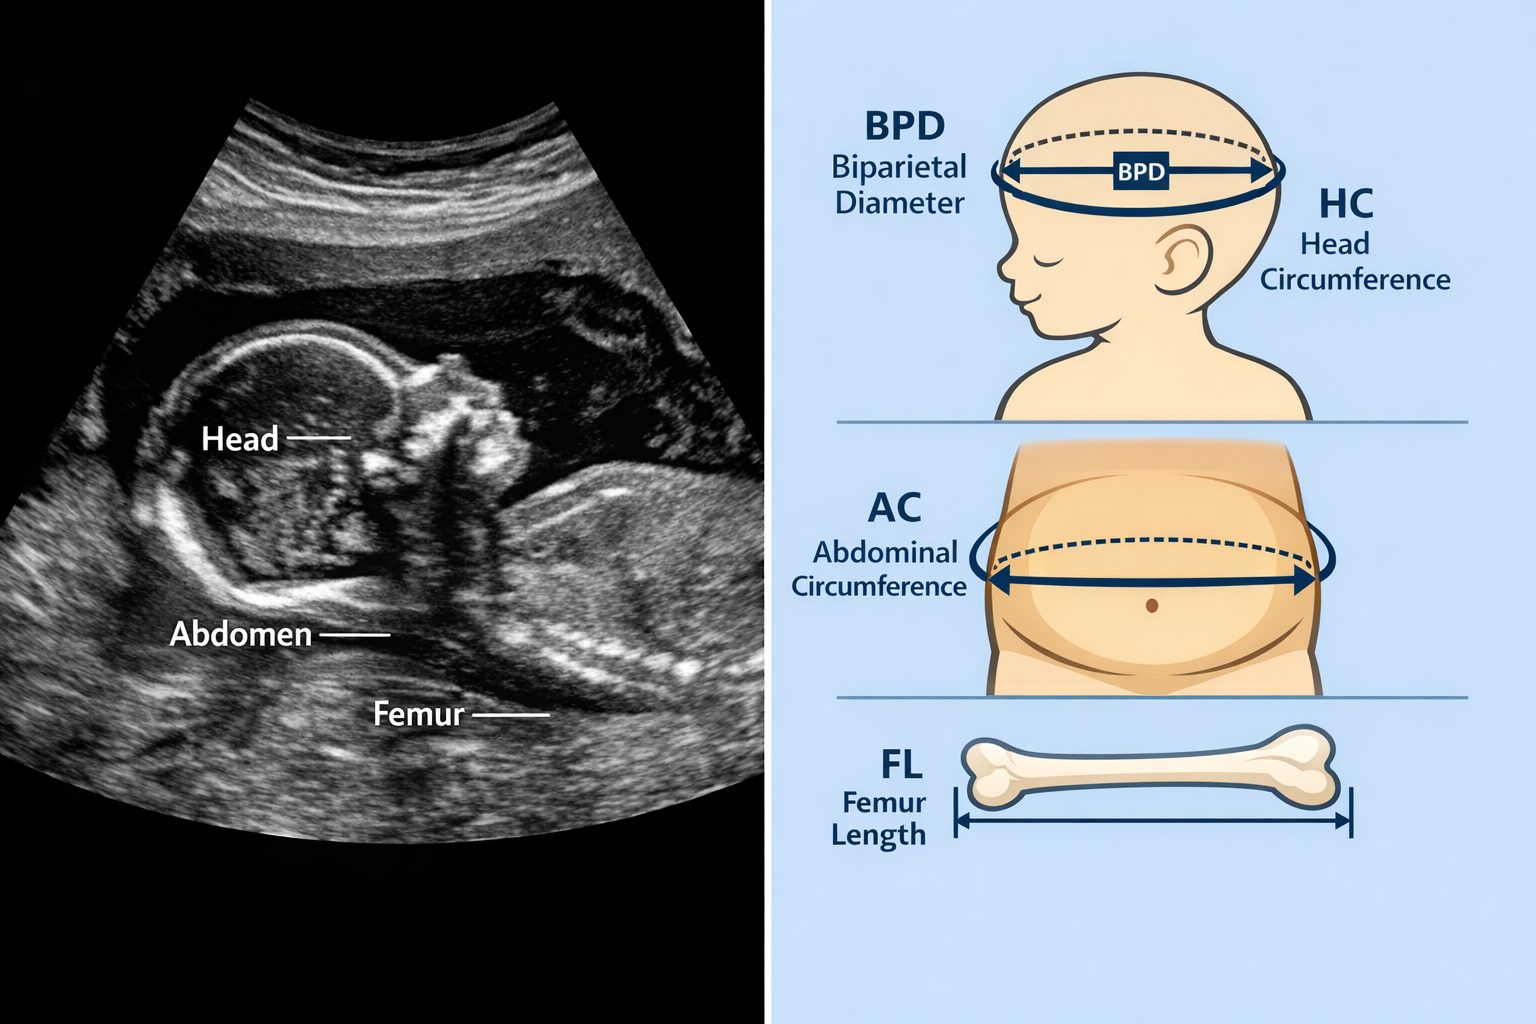

While the first-trimester Crown-Rump Length (CRL) offers the most accurate estimation of conception date, later trimester ultrasounds utilize various fetal biometrics to assess gestational age when an early scan wasn't performed or if there's a need to confirm growth. These measurements include Biparietal Diameter (BPD), Head Circumference (HC), Abdominal Circumference (AC), and Femur Length (FL). However, it's important to note that their accuracy for dating decreases significantly after the first trimester.

• Biparietal Diameter (BPD): This measures the widest part of the fetal head from one parietal bone to the other. It's measurable from about 12 weeks onward.

• Head Circumference (HC): The circumference measurement around the fetal head. Often used in conjunction with BPD.

• Abdominal Circumference (AC): Measures the circumference of the fetal abdomen at the level of the liver. This measurement is particularly sensitive to fetal growth and nutrition.

• Femur Length (FL): Measures the length of the longest bone in the body, the femur (thigh bone).